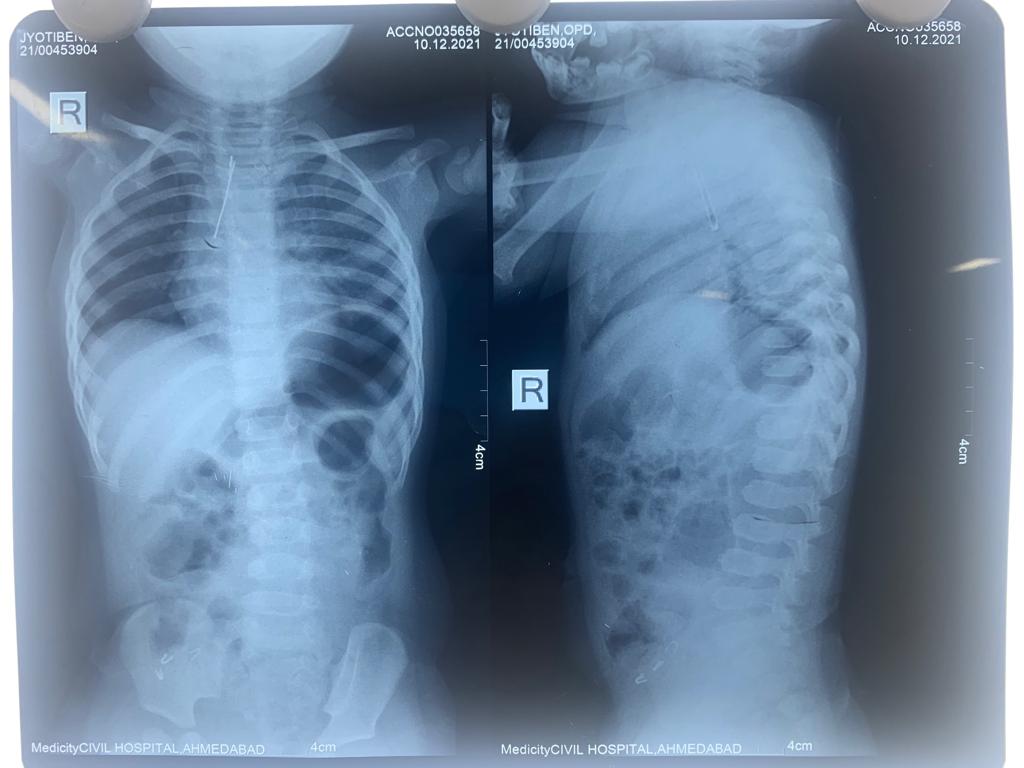

અમદાવાદ: ૨ વર્ષની બાળકી રમકડા સાથે રમતી વખતે LED બલ્બ ગળી ગઇ. જે શ્વાસનળી સુધી પહોંચ્યો. LED બલ્બના ઇલેક્ટ્રોડ્સના બંને છેડામાંથી એક છેડો જમણી બાજુના ફેફસામાં જ્યારે અન્ય છેડો શ્વાસનળીમાં ફસાઇ ગયો.ભારે જહેમત ઉપાડીને સિવિલ હોસ્પિટલના નિષ્ણાંત તબીબોની ટીમે સર્જરી હાથ ધરીને બલ્બ સફળતાપૂર્વક દૂર કર્યો. ૧૦ મી ડિસેમ્બરે બે બાળકો બાહ્ય પદાર્થ ગળી જવાની ફરિયાદ અને દુખાવા સાથે અમદાવાદ સિવિલ હોસ્પિટલમાં સારવાર અર્થે આવી પહોચ્યા. ૨ વર્ષની જ્યોતિ જ્યારે રમકડા થી રમી રહી હતી ત્યારે રમત રમતમાં રમકડામાં લગાવેલ એલ.ઇ.ડી. બલ્બ ગળી ગઇ. તેની માતા રાજકુમારીબેનને આ બાબતની જાણ થતા તેઓ સત્વરે સધન સારવાર અર્થે સિવિલ હોસ્પિટલની ૧૨૦૦ બેડ હોસ્પિટલમાં આવી પહોંચ્યા. હોસ્પિટલમાં એક્સ-રે અને સી.ટી. સ્કેન કરાવવામાં આવ્યા જેમાં આ એલ.ઇ.ડી. બલ્બ શ્વાસનળીમાં ફસાઇ ગયેલ હોવાનું નિદાન થયું.આવા જ બીજા એક કિસ્સામાં મહેસાણાના હનુભાઇ વણઝારાની બે વર્ષની દિકરી હિનાને ત્રણ દિવસથી શ્વાસ લેવામાં તકલીફ પડી રહી હતી. સ્થાનિક હોસ્પિટલમાં સી.ટી. સ્કેન કરાવતા ખબર પડી કે સીંગનો દાણો શ્વાસનળીમાં ફસાઇ ગયો છે. જેને અત્યંત જટીલ અને નિષ્ણાંત તબીબો જ સર્જરી દ્વારા દૂર કરી શકશે. જેના સારવાર અર્થે હીનાના પિતાશ્રી બાળકીને સિવિલ હોસ્પિટલ લઇ આવ્યા.જ્યાં ડૉ. મહેશ વાધેલા અને એનેસ્થેસિયા વિભાગના ડૉ. કિરન પટેલે આ જટીલ સર્જરી પાર પાડવાની જહેમત ઉપાડીને તેને સફળતાપૂર્વક પાર પાડી. જ્યારે ૨ વર્ષીય જ્યોતિની સમસ્યા અત્યંત જટીલ હોવાથી સિવિલ હોસ્પિટલના સુપ્રીટેન્ડેન્ટ અને બાળરોગ સર્જરી વિભાગના વડા ડૉ.રાકેશ જોષી અને તેમની ટીમે એનેસ્થેસિયા વિભાગના ડૉ. સીમા ગાંધી ના સહયોગથી સમગ્ર સર્જરી હાથ ધરીને સફળતાપૂર્વક પાર પાડી.ડૉ. રાકેશ જોષી દરેક માતા-પિતાને પાંચ વર્ષથી નાના બાળકોને રમકડા, સંવેદનશીલ પદાર્થો થી દૂર રાખવા અનુરોધ કરે છે. આવા પદાર્થો બાળક જ્યારે ગળી જાય ત્યારે ઉપરોક્ત કિસ્સા મુજબ ઘણી વખત શ્વાસનળીમાં પ્રવેશે છે. જેનાથી બાળક ગંભીર મુશકેલીમાં મુકાઇ શકે છે. અગાઉ એસિડ અને અન્ય જવલંત પદાર્થો ભુલથી ગળી જવાના કિસ્સા પણ સામે આવતા હતા. આ તમામ પ્રકારની તકલીફોથી બચવા માટે સાવચેતી એ જ સલામતીને ધ્યાને રાખીને પોતાના બાળકની સારસંભાળ રાખવાની ડૉ. જોષી સલાહ આપે છે.